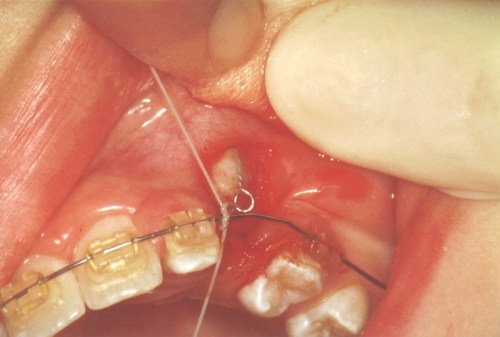

Nedenfor ses en billedserie, der illustrere forløbet.

- Hjørnetanden opereres frem og trækkes på plads med en elastik ned til en fast bøjle.